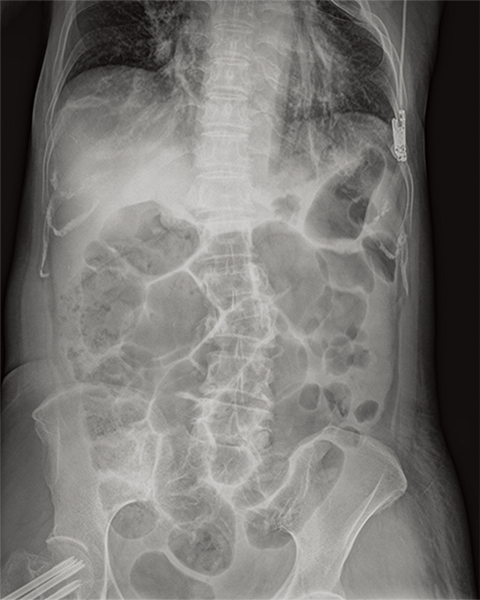

Multiple body parts supported

Abdomen

Cervical Spine

Thoracic Spine

Lumber Spine

Dynamic Visualization II

Optimizes image quality using latest Exposure Data Recognizer

Advanced recognition algorithms using automatic  calculations of estimated 3D image data, identify the body part required and adjusts contrast, density and enhancement for optimised image display. (Option)

Comparison of Dynamic Visualization II vs. conventional processing images (Lumbar Spine)

Comparison of Dynamic Visualization II vs. conventional processing images (Hip Joint)